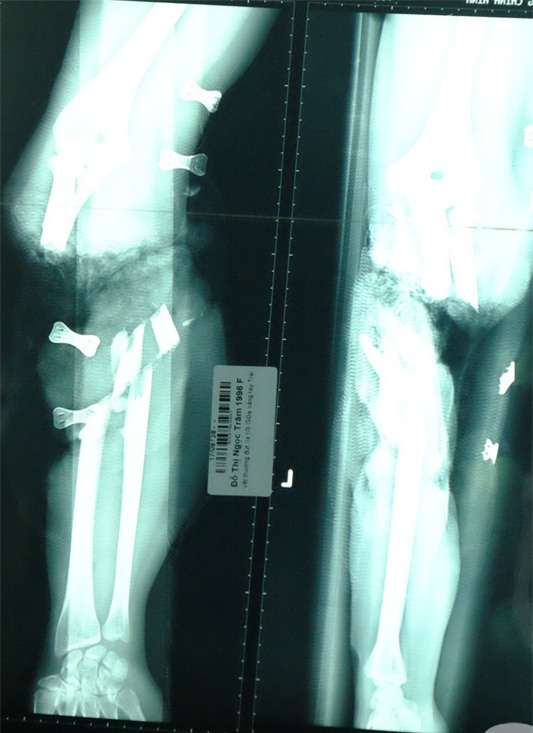

Khi bị tai nạn đứt rời chi, thời gian vàng (tối đa là 6 tiếng) là yếu tố quyết định việc có giữ lại được bộ phận đứt rời hay không. (Ảnh minh họa). |

Theo BS Khánh, từ lúc bệnh nhi gặp nạn đến khi được chuyển đến BV Chấn thương Chỉnh hình TP.HCM là 20 giờ. Vì đã qua thời gian vàng nên cánh tay của bệnh nhi không thể cứu vãn.